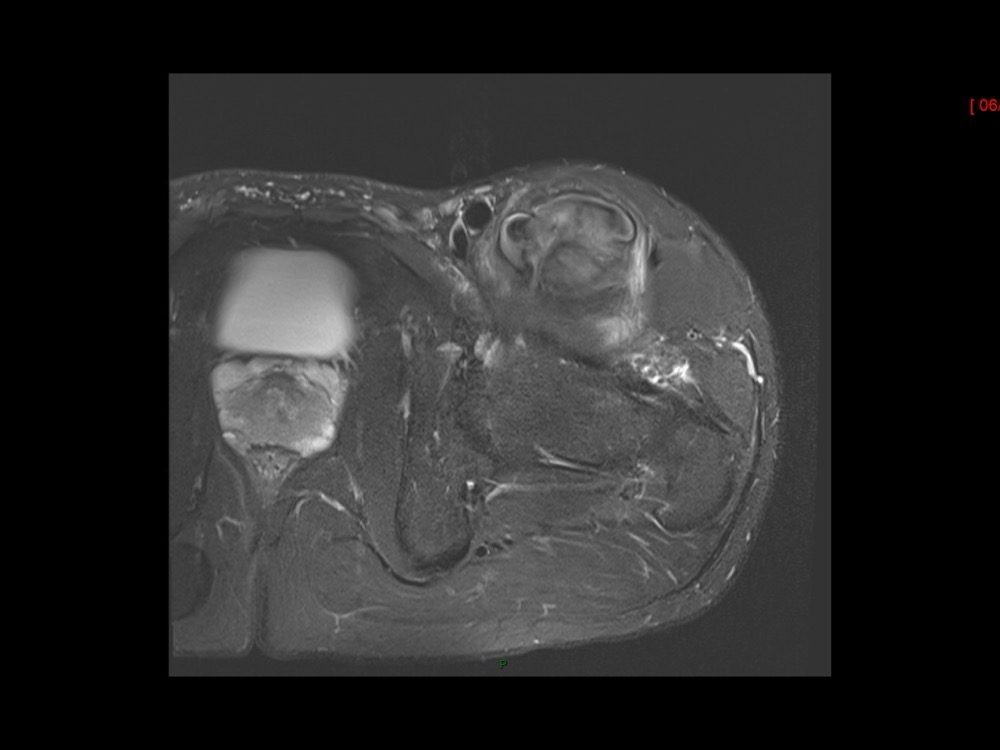

Moalla / Mihoubi-Bouvier / Drapé 18/05/2022